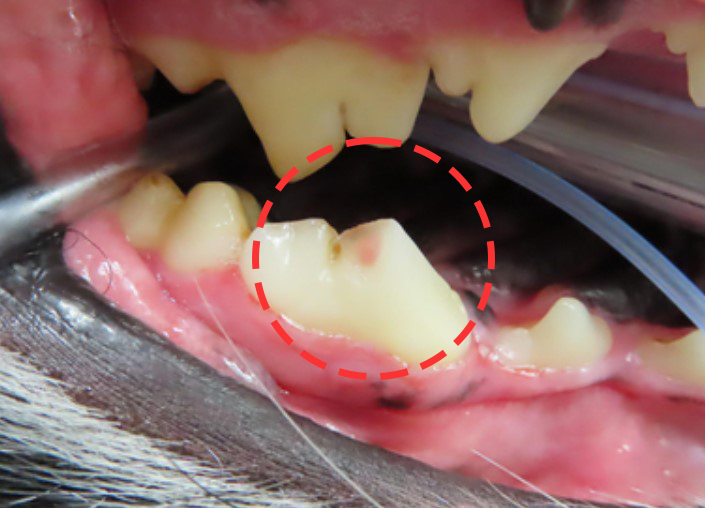

이 아이는 보호자분께서 골절 시점을 정확하게 알고

계시고 치수 윗부분의 감염만 확인되었기에

치수 절단술 치료를 진행하였습니다.

사진의 분홍색으로 보이는 부분이 신경이 노출된

골절 부위입니다.